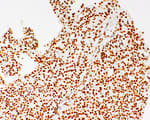

Mouse anti-CD45RO Monoclonal Antibody, Purified [UCHL-1]

Bethyl Laboratories Catalog # A500-020A A500-020A-T A500-020ACF

ValidatedDocuments (7)Mouse anti-CD45RO Monoclonal Antibody, Purified [UCHL-1]

Validation Performed

All Bethyl Laboratories® antibodies are validated to meet our strict performance standards.

Target: CD45RO

Reactivity: Human

Applications:

Platforms: COMET™, PhenoImager™ HT

Host: Mouse

Conjugate:

Purity:

For ordering information, see our International Distributors

Product has been discontinued